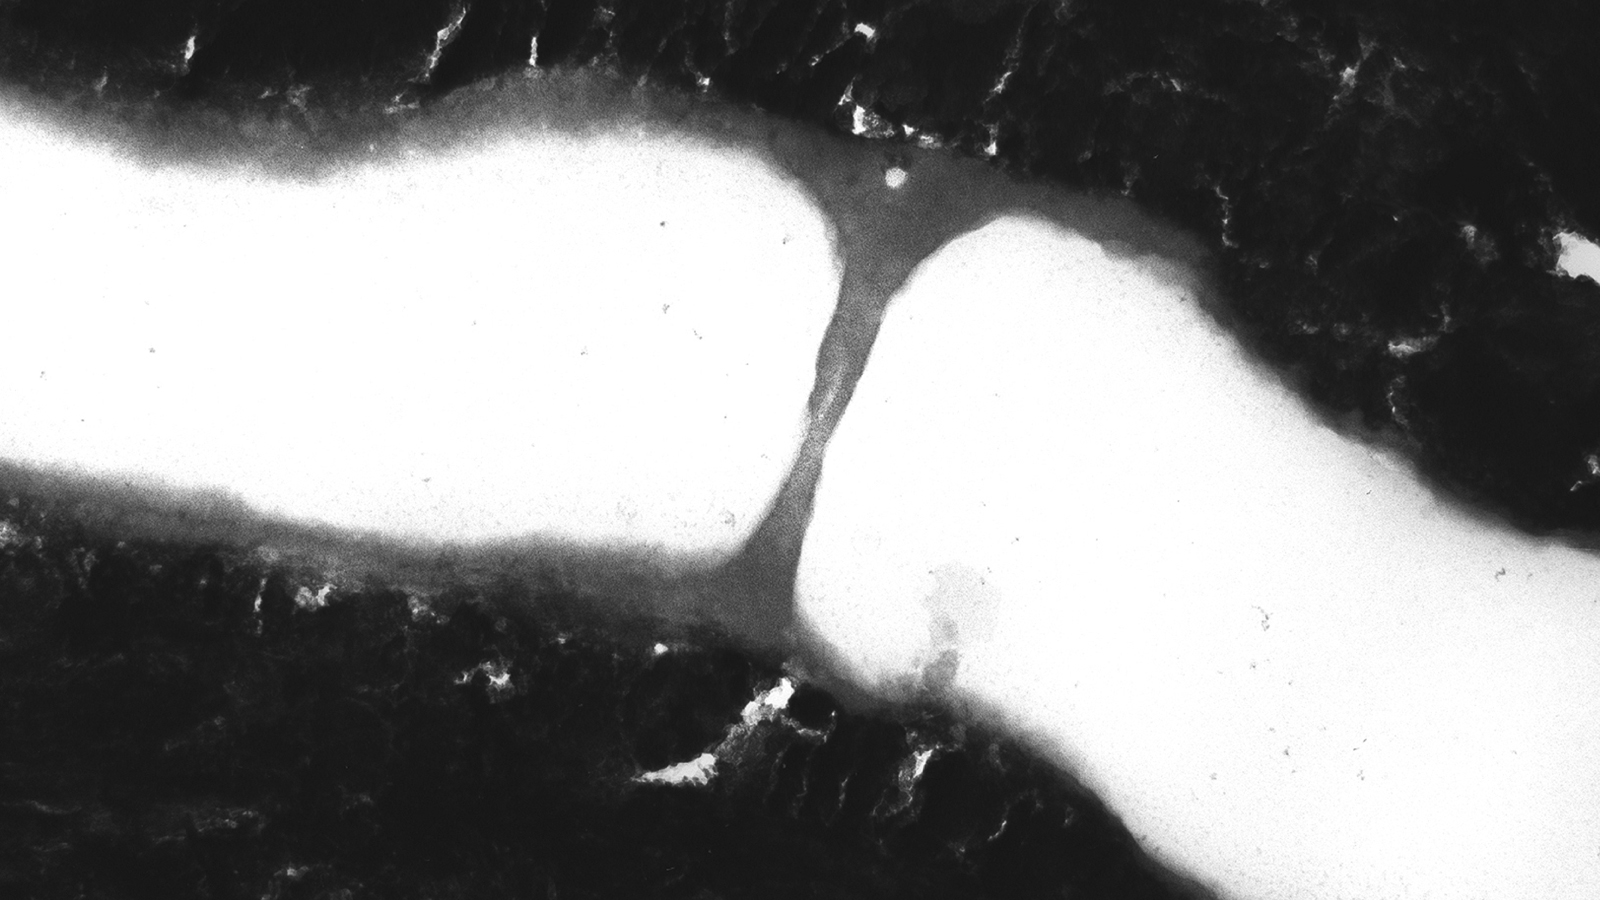

Schematic representation of effect

Schematic representation of effect:

Blue: Intradental sealing induced by GLUMA Desensitizer within dentinal tubuli

Image dentinal tubuli